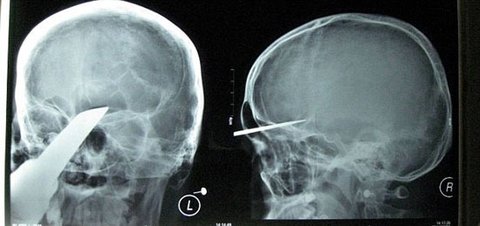

이마에 칼 꽂힌 소년

이마에 칼이 꽂힌 소년이 집에서 400km나 떨어진 병원구급차로 운반되어 수술을 받고 무사히 목숨을 건졌다.

이소년은 후난 성 창사에 사는 15세 되장빈(가명)의 집에 친구 3명이 놀러왔는데

그 중 한명이 신기하게 생긴 검을 가지고 왔다가 자랑하던도중

3~4m 쯤 떨어진 거리에서 머리에 그 칼이 박혀버리는 사고가 발생.

새벽 3시쯤 수술 시작해서 7시에 무사히 수술이 끝남

다행히 신경쪽을 건드리지 않아서 무사히 끝났다고 함